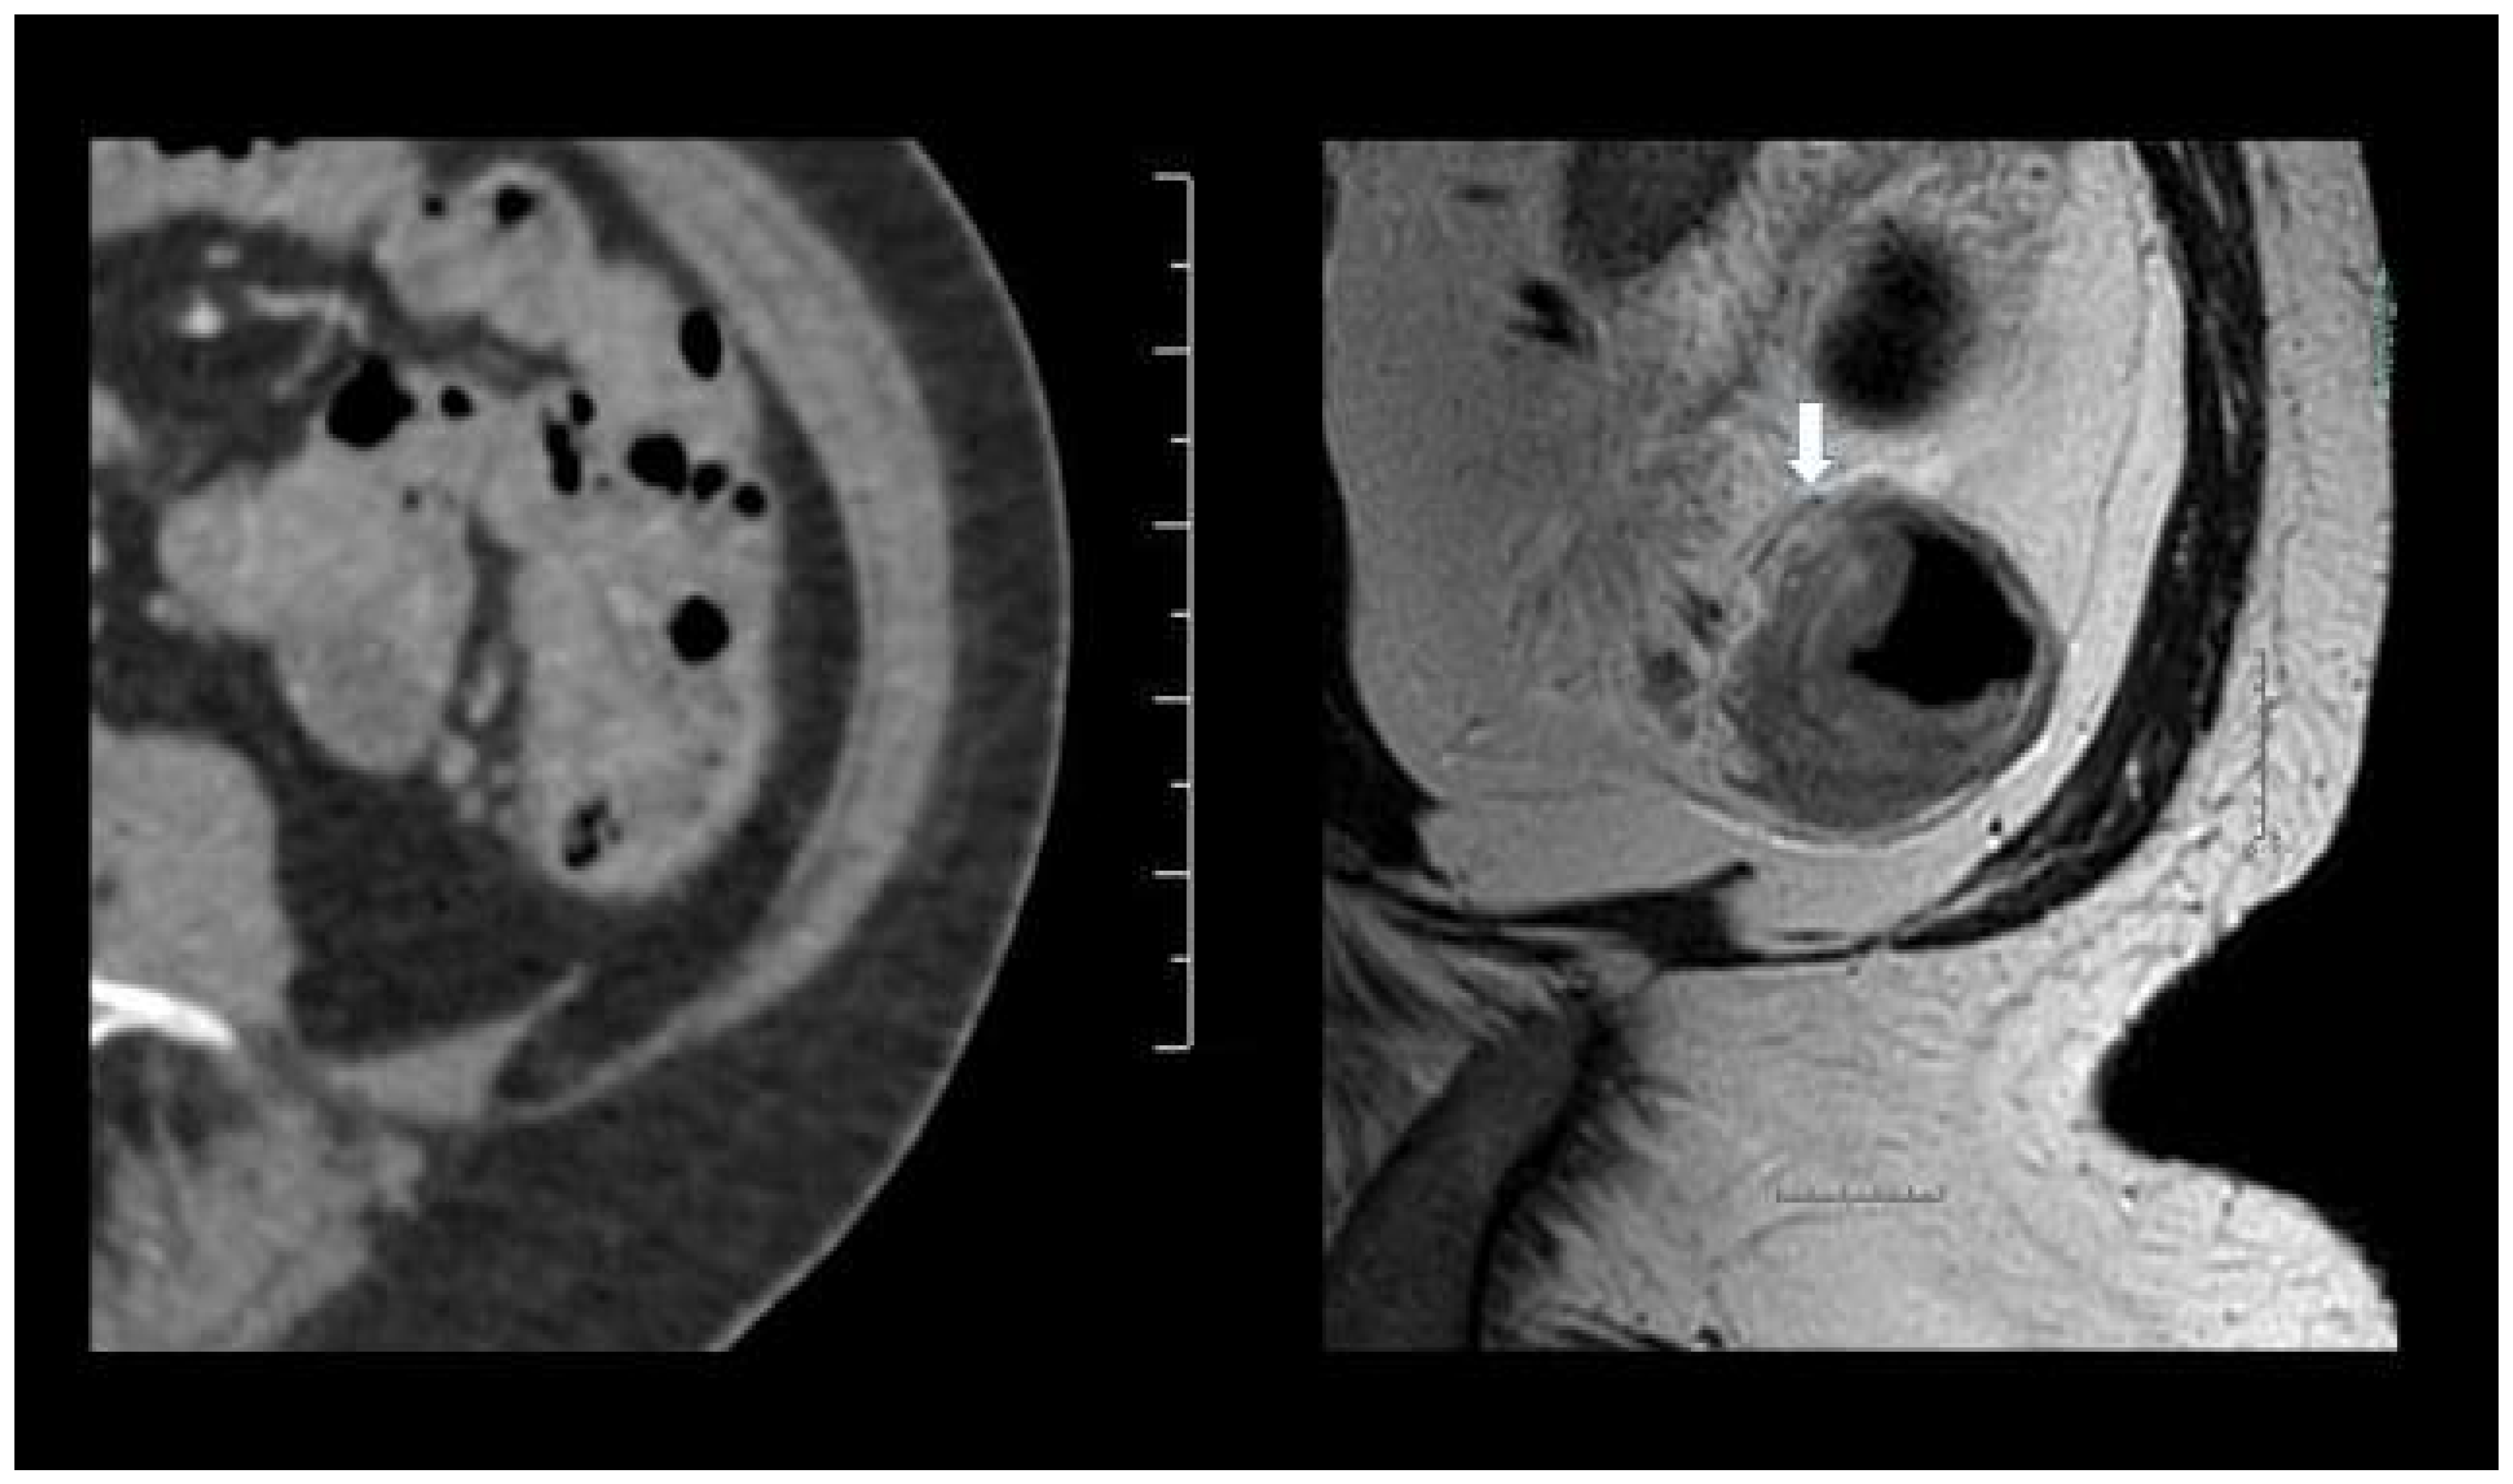

3. Results

3.2. Sensitivity and Specificity

3.3. Diffusion Weighted MRI